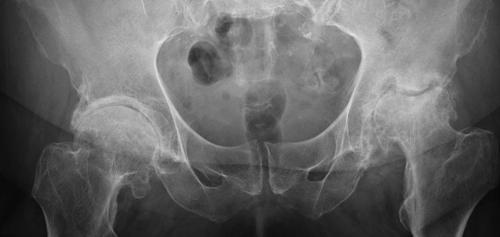

- рентгенологическое исследование . Позволяет визуализировать состояние головки бедра, выявить признаки остеофитов;

Последняя стадия коксартроза левого сустава (на фото — справа). Обратите внимание: головка сустава имеет впадину.

Коксартроз — прогрессирующее заболевание. Выявив его на ранних сроках и прибегнув к медикаментозному лечению, получить гарантию полного выздоровления невозможно.Болезнь можно приостановить, но через 5-10 лет механизм снова запускается.

Почему операции не избежать в 99% случаев? Потому что боль появляется только тогда, когда сустав уже имеет минимум 2-ю степень разрушения. А при такой степени ничего, кроме удаления сустава, не помогает. Специфика болезни такова, что на ранних стадиях она не диагностируется, потому что нет жалоб со стороны пациента.